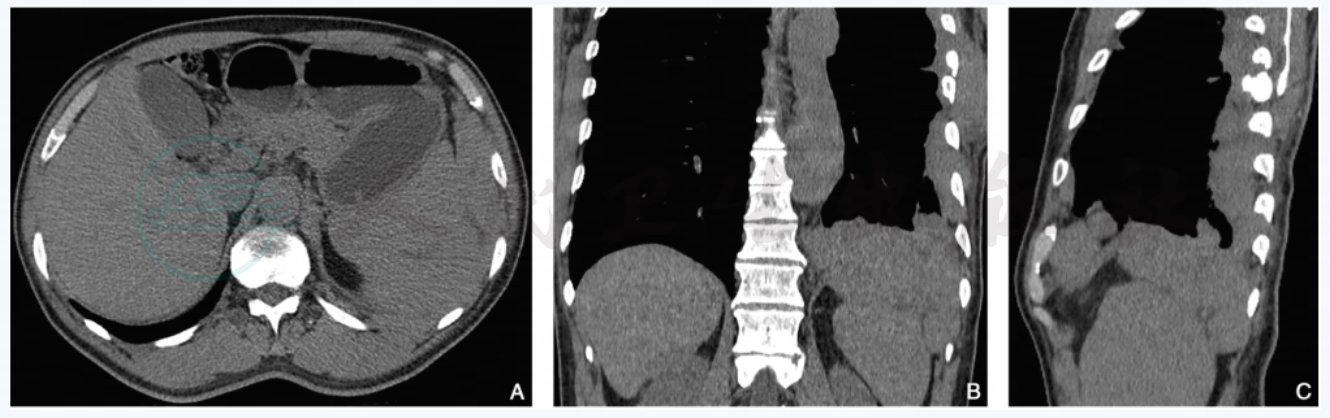

图3 膈肌转移瘤、肝脏转移瘤(肺癌)

注:男性,56岁,CT增强横断面动脉期(A)及静脉期(D)示左侧膈肌脚有一类椭圆形结节影,密度不均,冠状位重建动脉期(B)、静脉期(E)及矢状位重建(C)、静脉期(F)显示结节与膈肌脚关系;此外,肝右叶下段可见一小转移瘤结节。